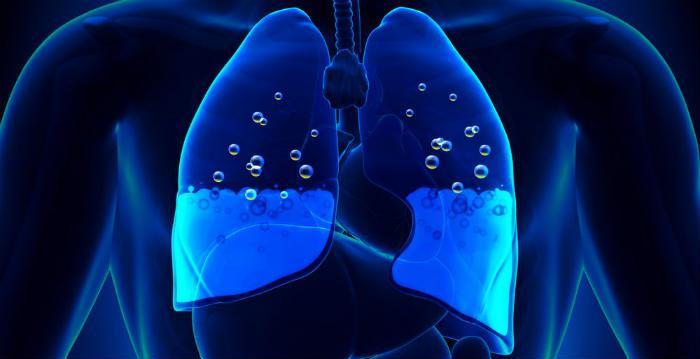

Отек легких (ОЛ) – это клинический синдром, связанный с накоплением излишней жидкости в интерстициальной ткани и/или альвеолах и проявляющийся нарушениями процесса газообмена в легких, ацидозом (смещением кислотно-щелочного резерва крови в кислую сторону) и гипоксией органов и тканей.

В основе патологического механизма развития основную роль играют нарушения проницаемости мембраны между альвеолами и капиллярами, снижение коллоидно-осмотического и увеличение гидростатического давления в сосудах микроциркуляторного русла.

В начальной стадии происходит пропотевание транссудата в интерстициальную легочную ткань. Избыточное его накопление и обуславливает развитие сердечной астмы (интерстициального отека легких).

Дальнейшее нарастание отечности тканей способствует проникновению транссудата в полость альвеол, где он смешивается с воздухом с образованием пены. Эта пена и препятствует нормальному газообмену. Данная стадия называется альвеолярным отеком.

На фоне нарастающей одышки происходит прогрессирующее снижение внутригрудного давления. Это усиливает приток крови к правым отделам сердца и вызывает прогрессирования застоя в сосудах малого круга кровообращения. В свою очередь, это способствует дальнейшему нарастанию отечности интерстициальных тканей, происходит формирование порочного круга.